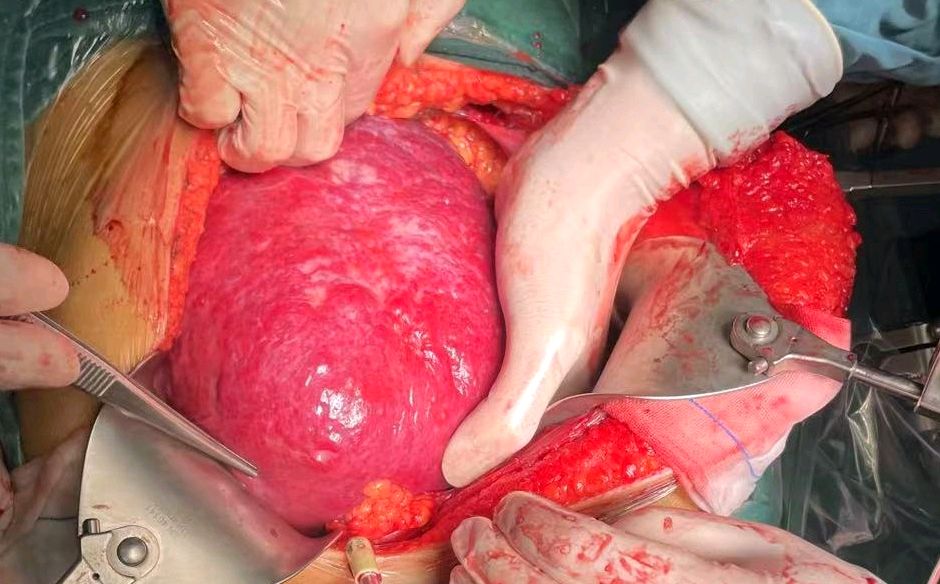

2. **手术方法**:传统上,巨大肝血管瘤多采用开腹切除的方式,手术切口可能超过30cm,这种方法创伤大、出血多、恢复周期长。近年来,随着腹腔镜技术的进步,微创腔镜手术逐渐成为另一种选择。微创手术可以减少创伤,缩短术后恢复周期,但对手术团队的技术要求较高,需要面对手术视野窄、操作空间狭小等挑战 。

3. **手术风险与处理**:巨大肝血管瘤手术风险较大,特别是出血问题。因此,控制出血是手术中的一个重要环节。术前可考虑进行肝动脉栓塞治疗,以缩小肝脏体积,提高手术安全性。肝动脉栓塞还可以使血管瘤硬化,有助于保障手术安全 。